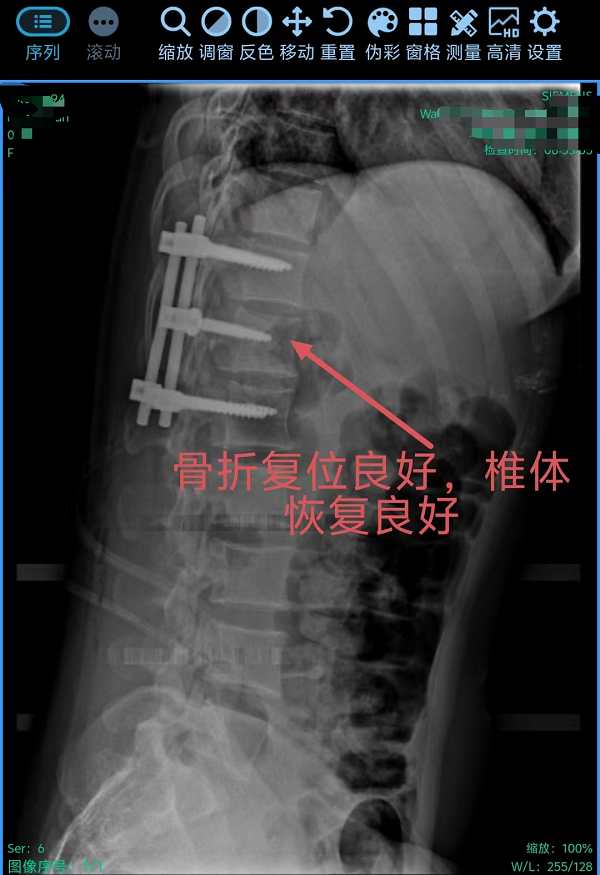

在丁晔副主任医师带领下,团队联合彭晴医师等医护人员,成功完成3台分属颈、胸、腰椎三大区域的高难度脊柱外科手术,病种涵盖退行性病变与创伤性骨折,融合微创内镜与经典开放技术,彰显科室综合诊疗实力。

3. 为胸椎爆裂性骨折患者施后路切开复位、微创减压内固定术(四级手术),胸椎爆裂性骨折常因高能量损伤导致,骨折块可能突入椎管压迫脊髓,致残风险高。丁晔副主任医师团队采用微创理念进行减压,并完成了有效的复位与坚强的内固定,既解除了对神经的压迫,又最大程度地减少了手术创伤,为患者争取了最佳的神经功能恢复条件。

三台手术均顺利完成,患者术后恢复良好,标志着我院脊柱疾病微创化、精准化治疗迈上新台阶。